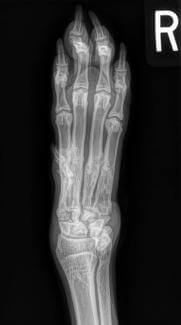

Thoracic Limb Fractures

Metacarpus